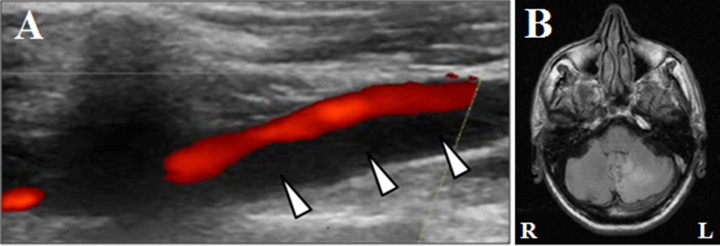

A. Cervical ultrasound of a patient with a dissection of the vertebral artery in the transition of V1 to V2 segments.